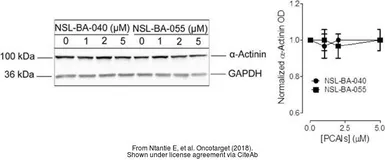

The data was published in the journal Oncotarget in 2018. PMID: 29899821

The data was published in the journal Oncotarget in 2018. PMID: 29899821

The data was published in the journal Oncotarget in 2018. PMID: 29899821

The data was published in the journal Oncotarget in 2018. PMID: 29899821

The data was published in the journal Oncotarget in 2018. PMID: 29899821

The data was published in the journal Oncotarget in 2018. PMID: 29899821

The data was published in the journal Oncotarget in 2018. PMID: 29899821